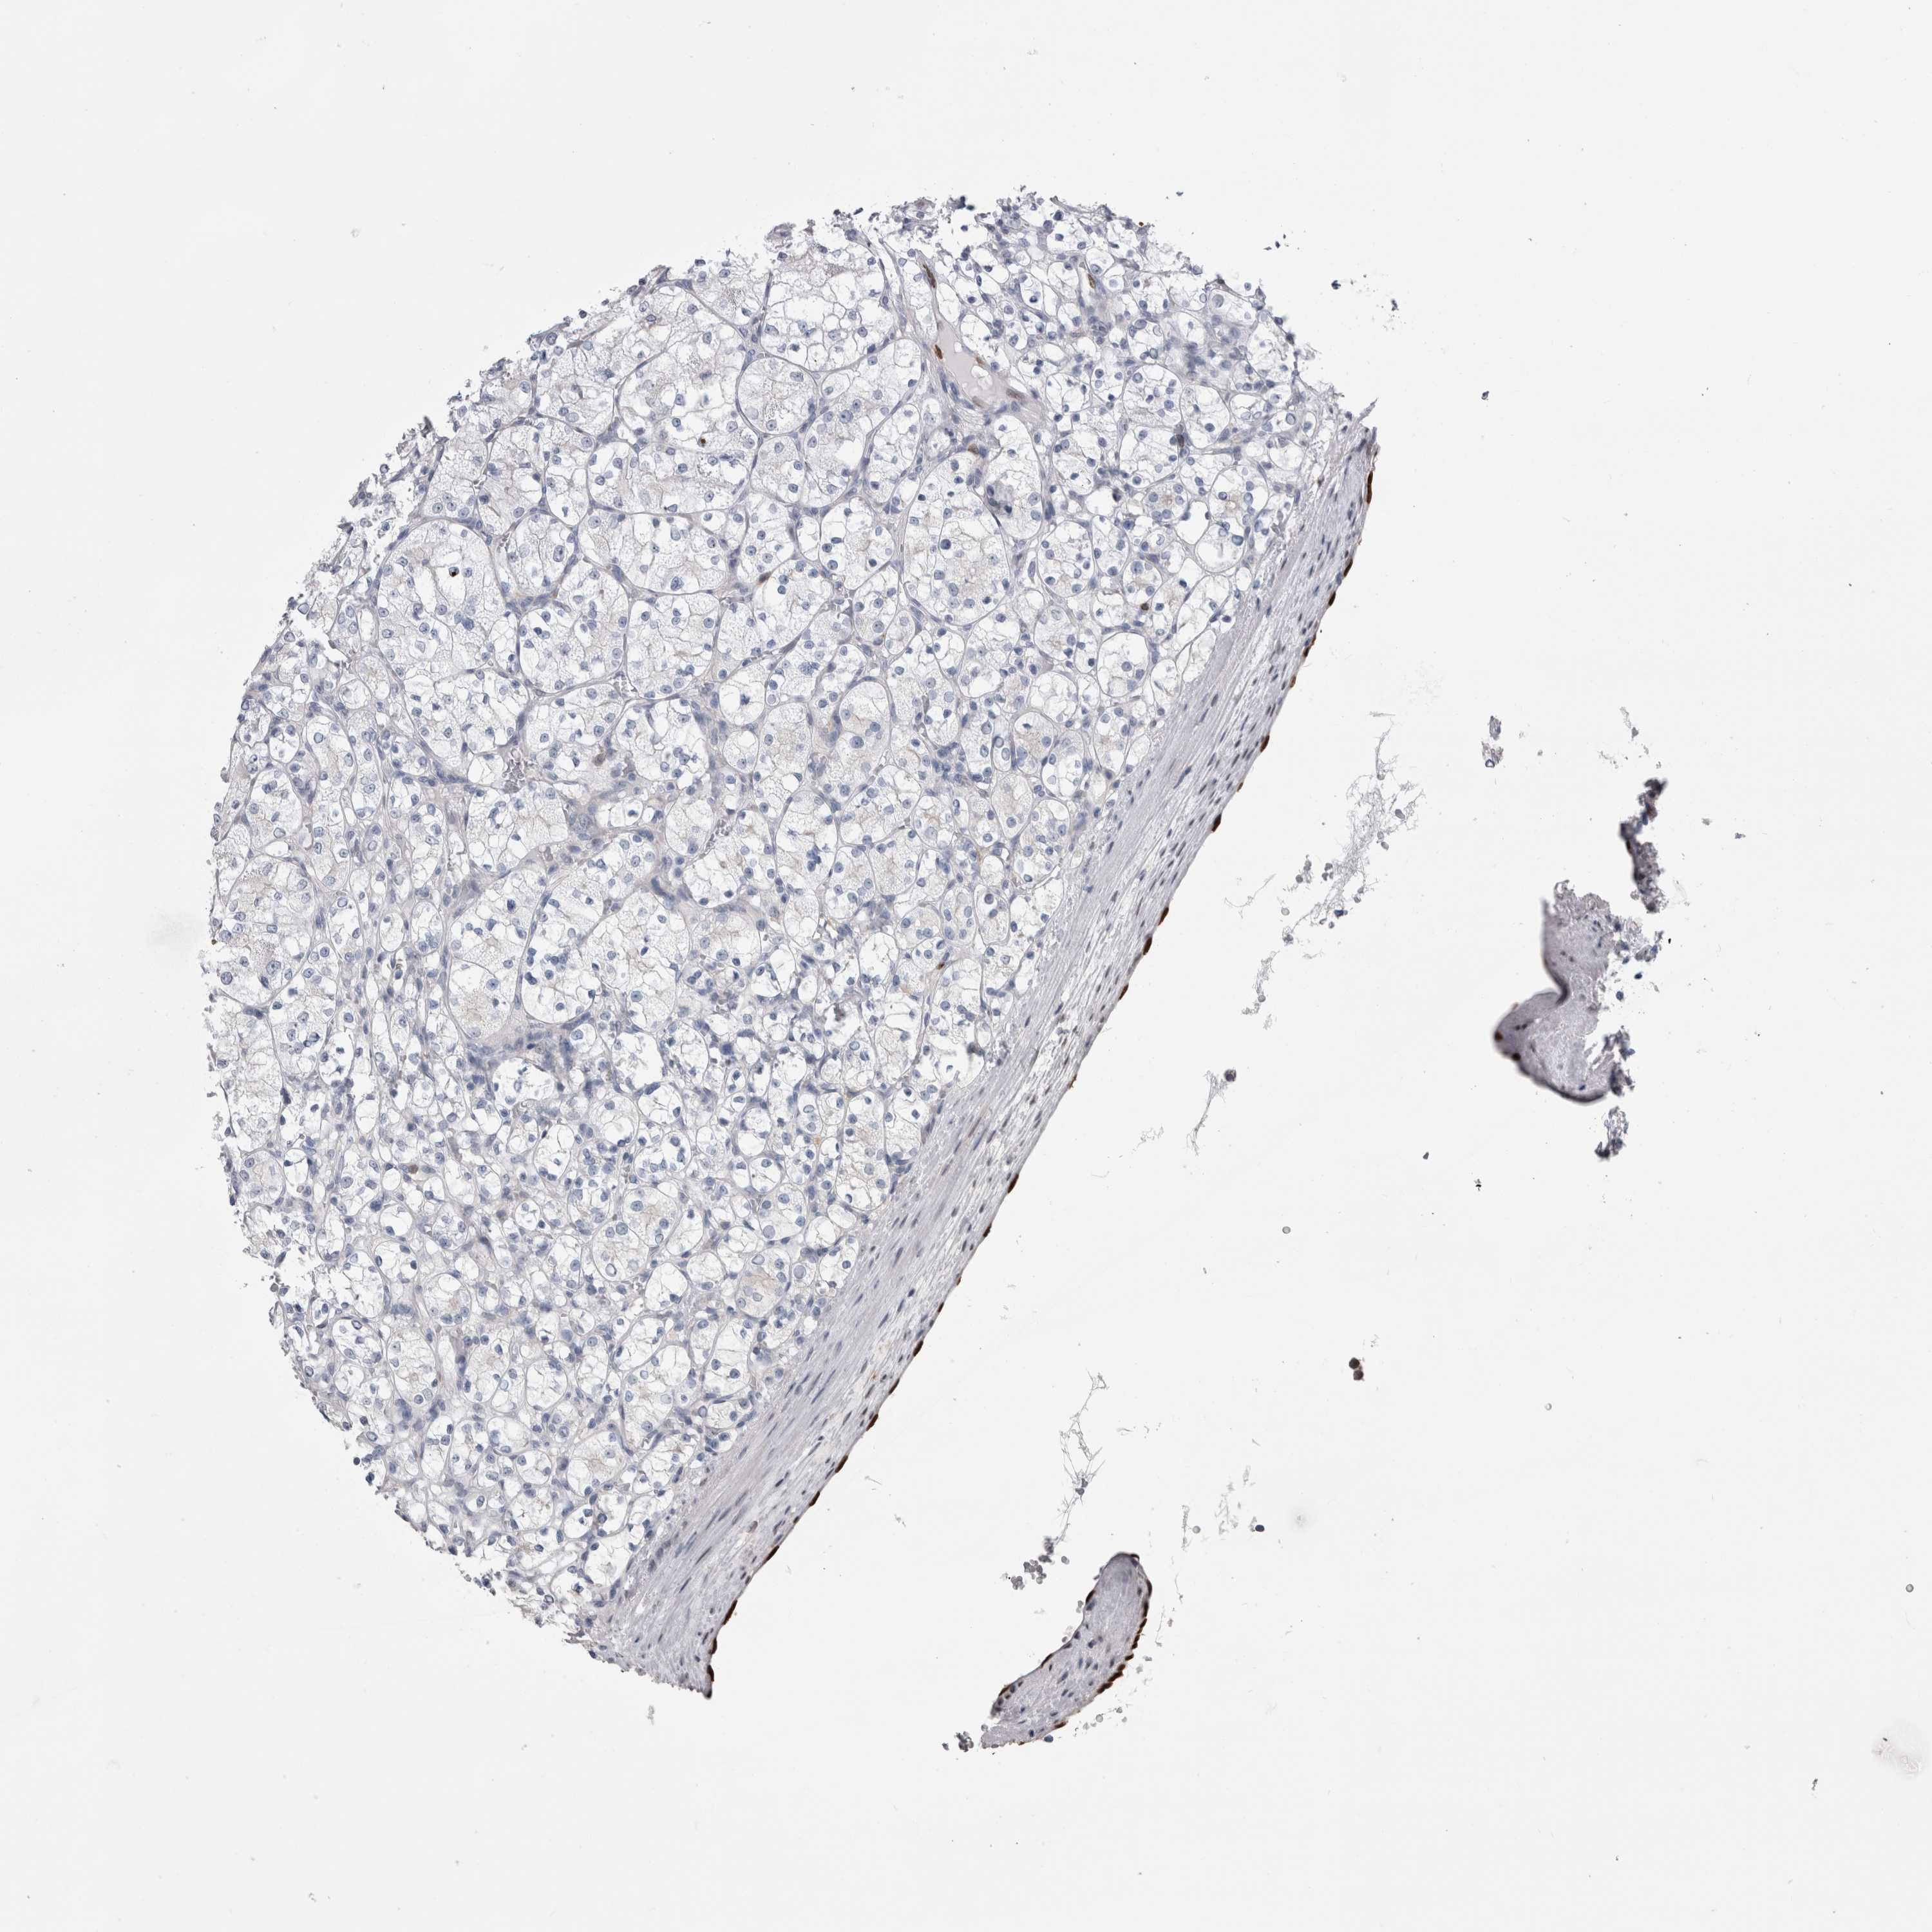

KIDNEY RENAL CLEAR CELL CARCINOMA (VALIDATION) - Interactive survival scatter ploti

The Survival Scatter plot shows the clinical status (i.e. dead or alive) for all individuals in the patient cohort, based on the same data that underlies the corresponding Kaplan-Meier plots. Patients that are alive at last time for follow-up are shown in blue and patients who have died during the study are shown in red.

The x-axis shows the expression levels (FPKM) of the investigated gene in the tumor tissue at the time of diagnosis. The y-axis shows the follow-up time after diagnosis (years). Both axes are complimented with kernel density curves demonstrating the data density over the axes. The top density plot shows the expression levels (FPKM) distribution among dead (red) and alive patients (blue). The right density plot shows the data density of the survived years of dead patients with high and low expression levels respectively, stratified using the cutoff indicated by the vertical dashed line through the Survival Scatter plot. This cutoff is automatically defined based on the FPKM cutoff that minimizes the p-score. The cutoff can be changed by dragging the vertical line or by entering a cutoff value in the square labeled "Current cut-off".

Under the Survival Scatter plot the p-score landscape (black curve; left axis) is shown together with dead median separation (red curve; right axis). Dead median separation is the difference in median mRNA expression between patients who have died with high and low expression, respectively. It is calculated as follows: median FPKM expression of dead patients with high expression - median FPKM expression of dead patients with low expression. This is intended to aid the user in visually exploring custom cutoffs and the associated p-scores and dead median separation.

Individual patient data is displayed and can be filtered by clicking on one or more of the category buttons on the top of the page. Categories describing expression level and patient information include: high, low, alive, dead, female, male and tumor stages. The scale of the x-axis can be toggled between linear and log-scale by clicking on the "x log" button. Mouse-over function shows TCGA ID, patient information and mRNA expression (FPKM) for each patient.

& Survival analysisi

Kaplan-Meier plots summarize results from analysis of correlation between mRNA expression level and patient survival. Patients were divided based on level of expression into one of the two groups "low" (under cut off) or "high" (over cut off). X-axis shows time for survival (years) and y-axis shows the probability of survival, where 1.0 corresponds to 100 percent.

IL33 is not prognostic in Kidney Renal Clear Cell Carcinoma (validation)

Best expression cut offi

: 13.33

P scorei

N/A

Average pTPM 10.7

Number of samples 100